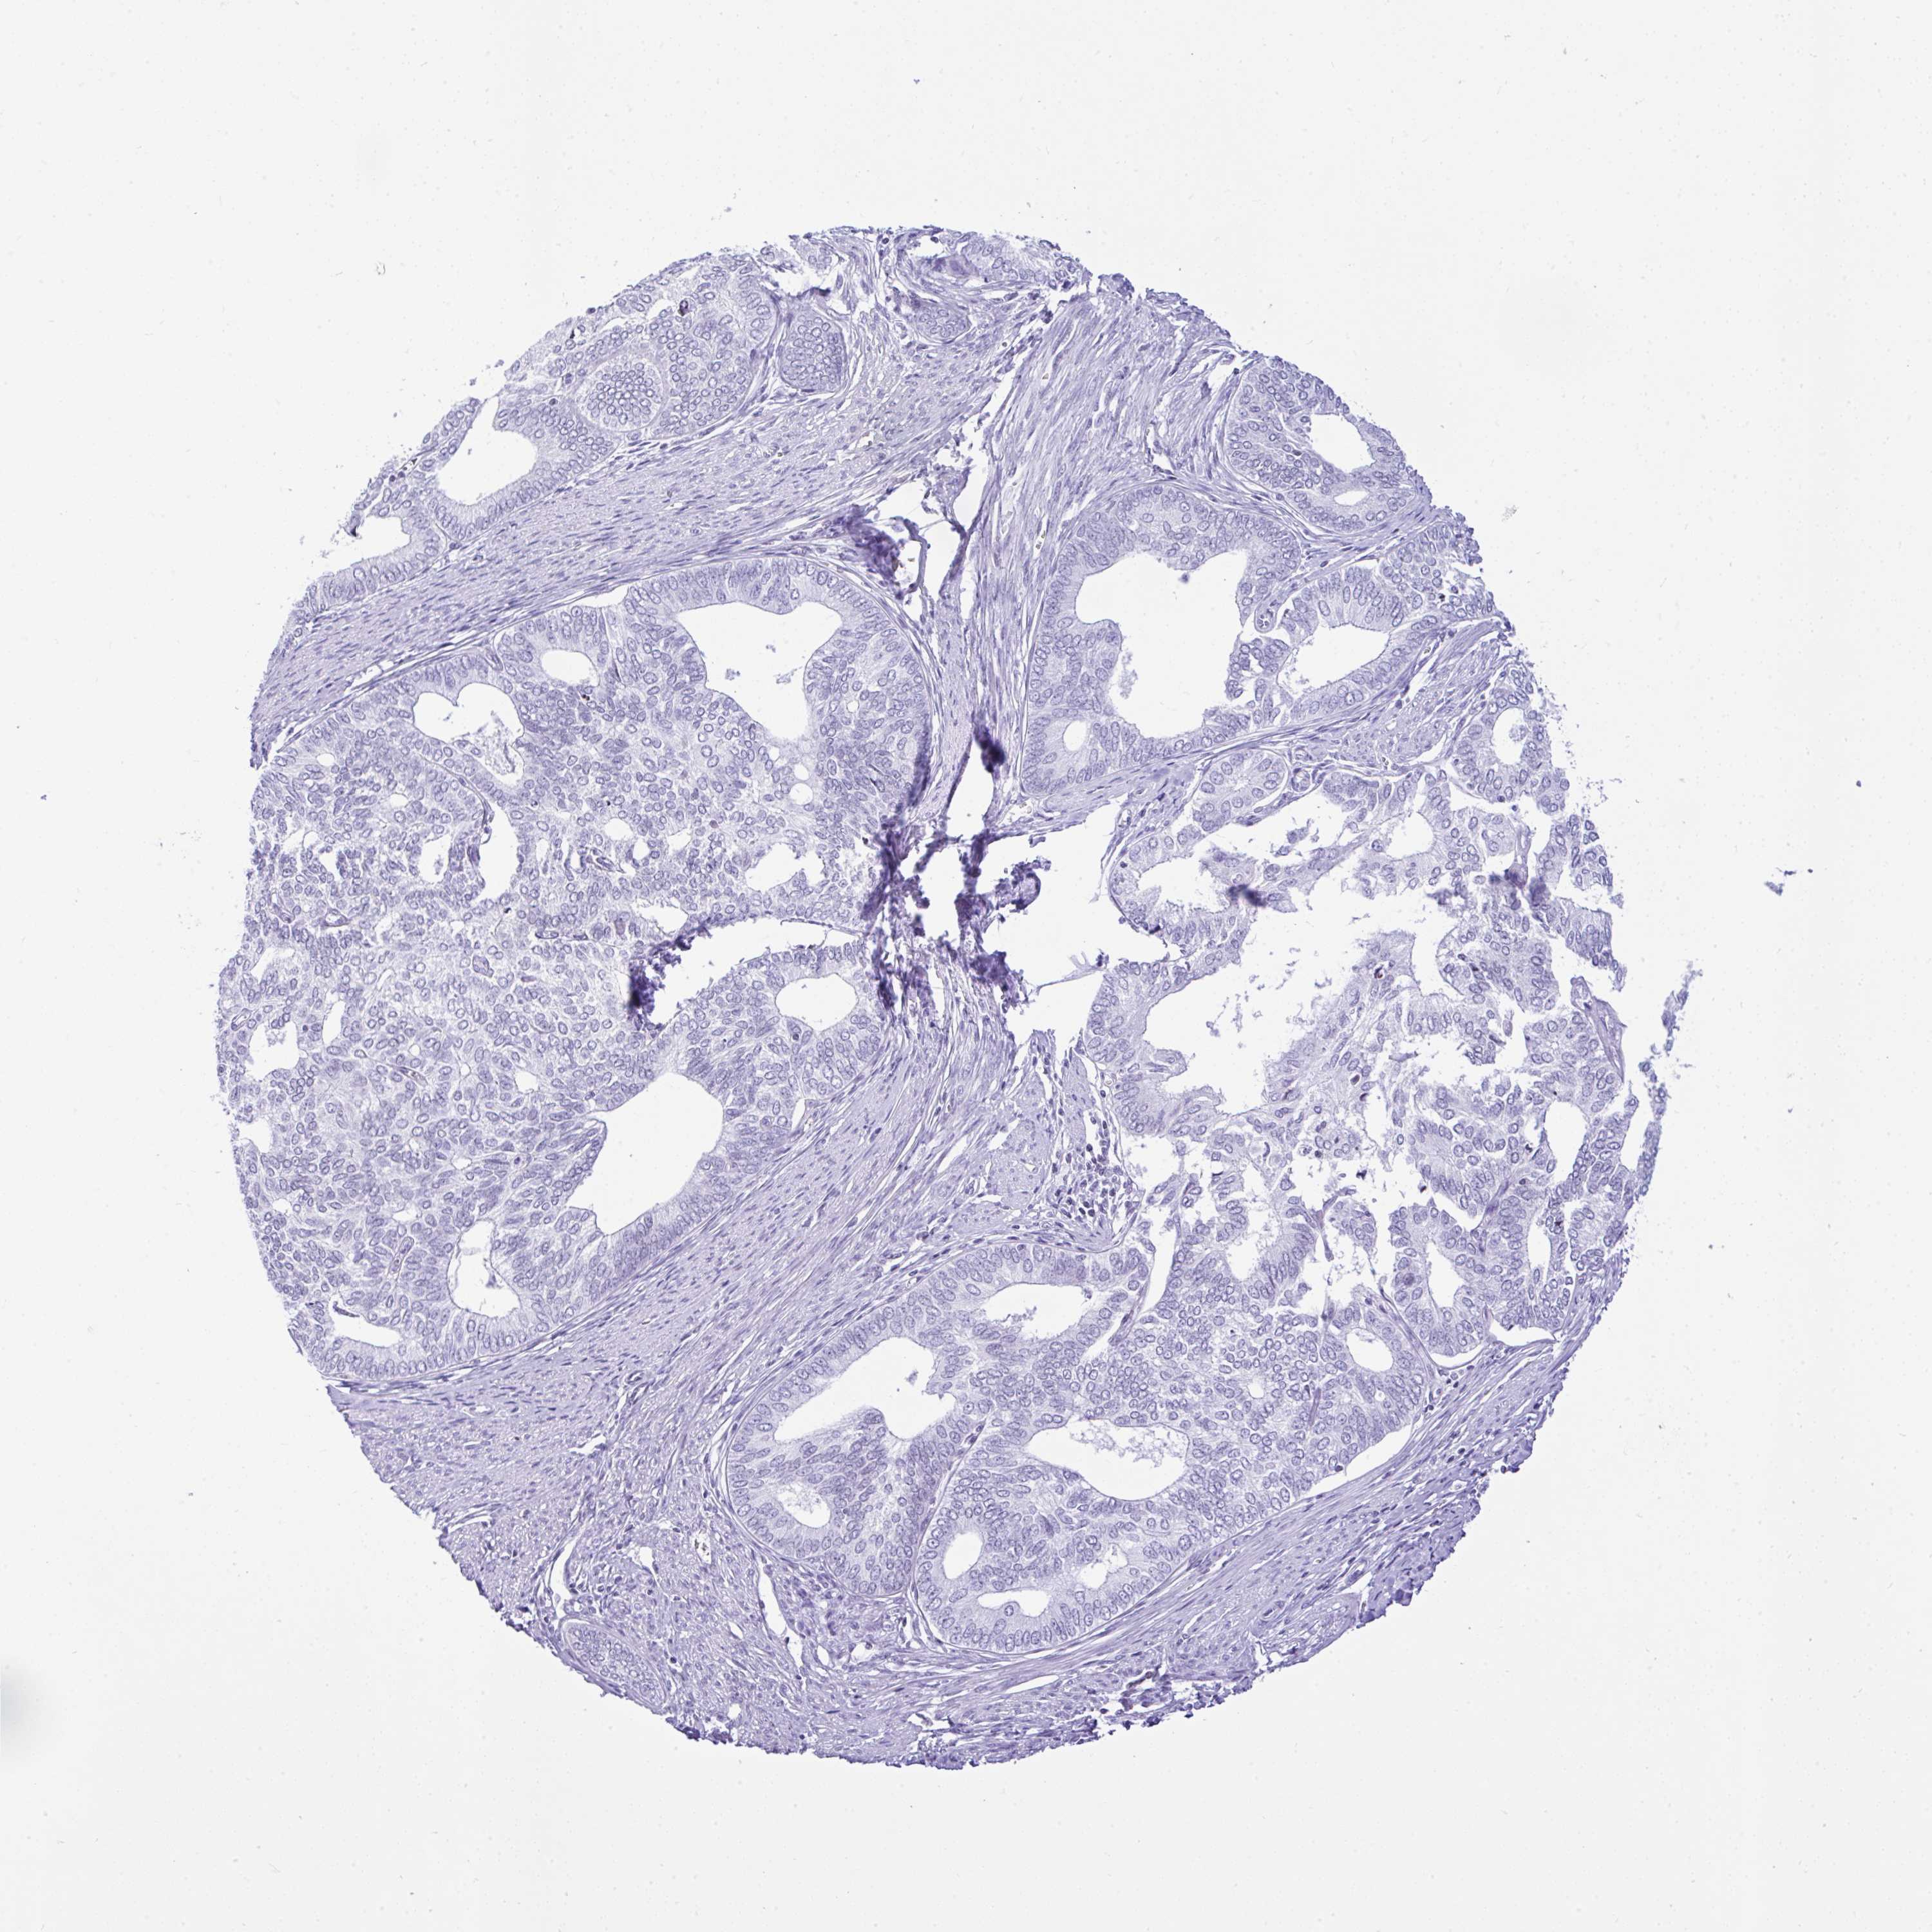

ENDOMETRIAL CANCER - Protein expressioni

A mouse-over function shows sample information and annotation data. Click on an image to view it in a full screen mode. Samples can be filtered based on level of antibody staining by selecting one or several of the following categories: high, medium, low and not detected. The assay and annotation is described here.

Note that samples used for immunohistochemistry by the Human Protein Atlas do not correspond to samples in the TCGA dataset.

Antibody stainingi

Antibody staining in the annotated cell types in the current human tissue is reported as not detected, low, medium, or high, based on conventional immunohistochemistry profiling in selected tissues. This score is based on the combination of the staining intensity and fraction of stained cells.

Each image is clickable and will lead to virtual microscopy that enables deeper exploration of all samples and also displays staining intensity scores, fraction scores and subcellular localization as well as patient and tissue information for each sample.

Antibody HPA055114

Staining

High

Medium

Low

Not detected

Intensity

Strong

Moderate

Weak

Negative

Quantity

>75%

75%-25%

<25%

None

Location

Nuclear

Cytoplasmic/membranous

Cytoplasmic/membranous,nuclear

Adenocarcinoma, NOS

Carcinoma, NOS

Adenocarcinoma, metastatic, NOS